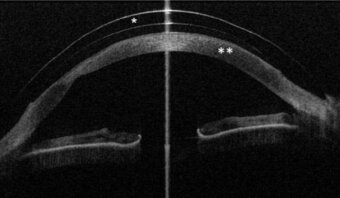

Das Vorderabschnitts-OCT des vorderen Augenabschnitts nach Anpassung einer Sklerallinse liefert ein "Schnittbild" durch die Sklerallinse (*) und Hornhaut (**). Man sieht nun, dass die Linse die gesamte Hornhaut überspannt, nur im Sklerabereich aufliegt und dass sich zwischen Linsenrückfläche und Hornhautvorderfläche ein flüssigkeits-gefüllter Raum befindet.